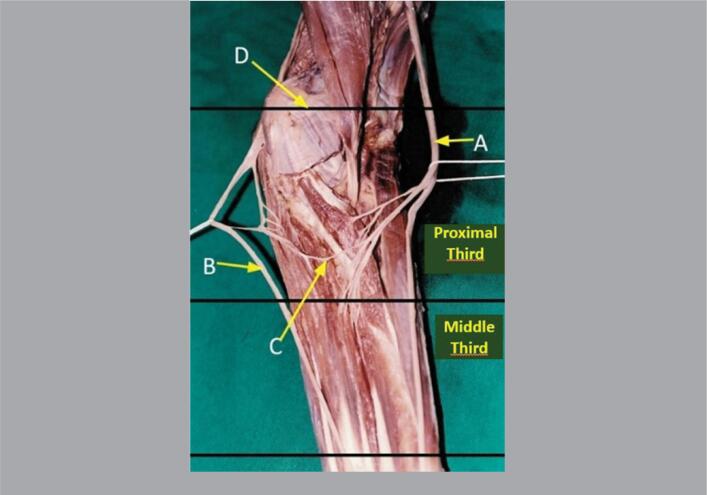

Methods: One hundred forearms from 50 adult cadavers were used in this study. Dissection was performed through a median incision in the forearm and distal third of the arm. Lines between the humeral epicondyles (interepicondylar) and between the styloid processes of the radius and ulna (interstyloidea) were used as reference points for the topographic location of the anastomoses, and the forearms were divided into proximal, middle and distal thirds.

Results: MGA was present in 27 forearms (27%). In four limbs (14.8%) the nerve fascicles originated from the median nerve proximal to the interepicondylar line. In two limbs (7.4%), at the level of the interepicondylar line and, in 21 of these (77.7%), they were found distal to this line. In 17 limbs (62.9%), the anastomosis occurred in the proximal third of the forearm, in eight limbs (29.6%), the anastomosis occurred in the middle third of the forearm and, in two limbs (7.4%), the anastomosis occurred with the ulnar nerve it occurred in the distal third of the forearm.

Conclusion: Despite the great variation in their location, most anastomoses were found distal to the interepicondylar line, especially in the proximal third of the forearm. Level of Evidence IV; Case Series.